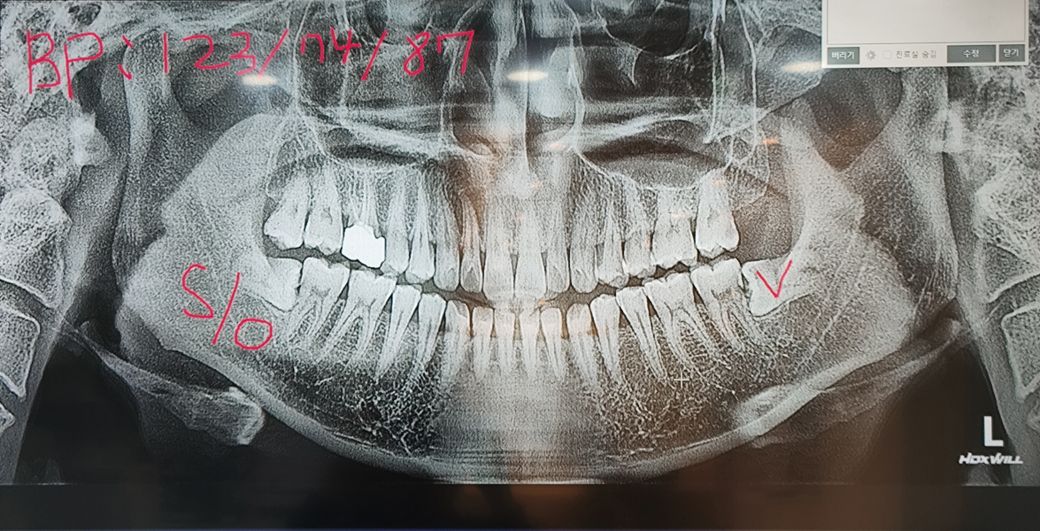

치아 사진보고 충치심각한지 한번봐주세요

위두장은 사랑니 뽑기전에 병원두곳에서 엑스레이 찍은사진인데 충치 심각한지 한번만 봐주세요

밑에 매복사랑니 두개는 20일전쯤 뽑아 지금은 없어용 근대 매복사랑니를 오래방치해 옆 어금니 인접면 충치가 생긴거 같은데 보시고 충지맞는지 알려주심 감사합니다.

사진상으로 위 오른쪽끝 어금니에서 네번째 이가 지금 밑사진 첫번째 검은 부분인데 이게 범랑질 안에서 어렸을때부터 충치가 자란거라하더라구요 상태가 심각한가요?

충치가 여러곳에서 관찰이 되고 있습니다. 파노라마 사진으로는 정확한 판별은 힘드니 치과를 몇곳 돌아보시고 결정하시는 게 좋겠습니다.

1. 아래 양쪽 두번째 큰 어금니는 매복사랑니로 인해 충치가 생긴 것은 맞는것으로 사진상 보입니다

2. 오른쪽 위 작은 어금니는 육안사진으로 봤을때 옆면 충치가 있을 것으로 예상됩니다 옆면 충치의 경우 진행이 빠르고 그 옆 치아에도 영향을 줄 수 있으므로 정지우식이 아닌이상 치료를 해주면 좋습니다

3. 치근단사진(작은 방사선 사진)을 찍어야 더 정확히 나옵니다